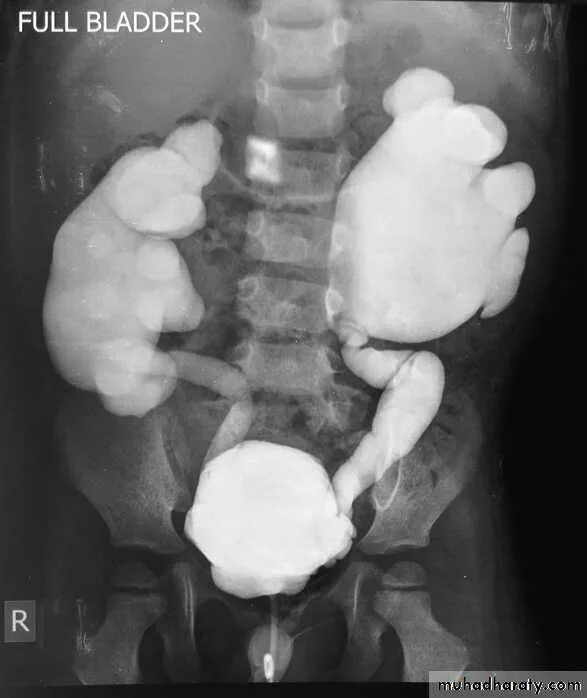

Мегауретер у детей что это